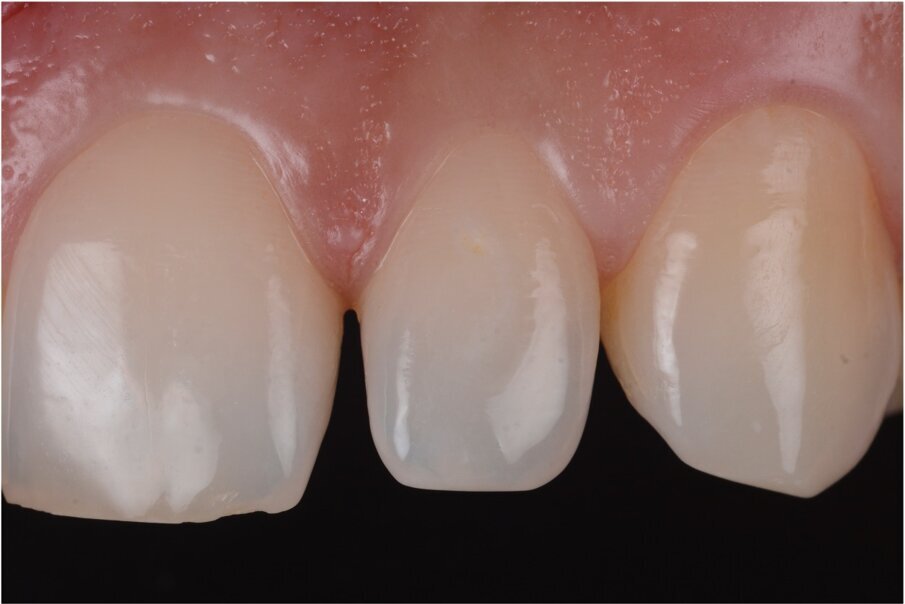

Fig. 5: Perfect emergency profile with front-wing technique. Courtesy of Dr. Jun Iwata, Japan.

You generate RETRACTION with the rubber dam on the most critical area which corresponds to the zenith and emergence profile, impossible to do with any kind of wax-up (Fig. 5).